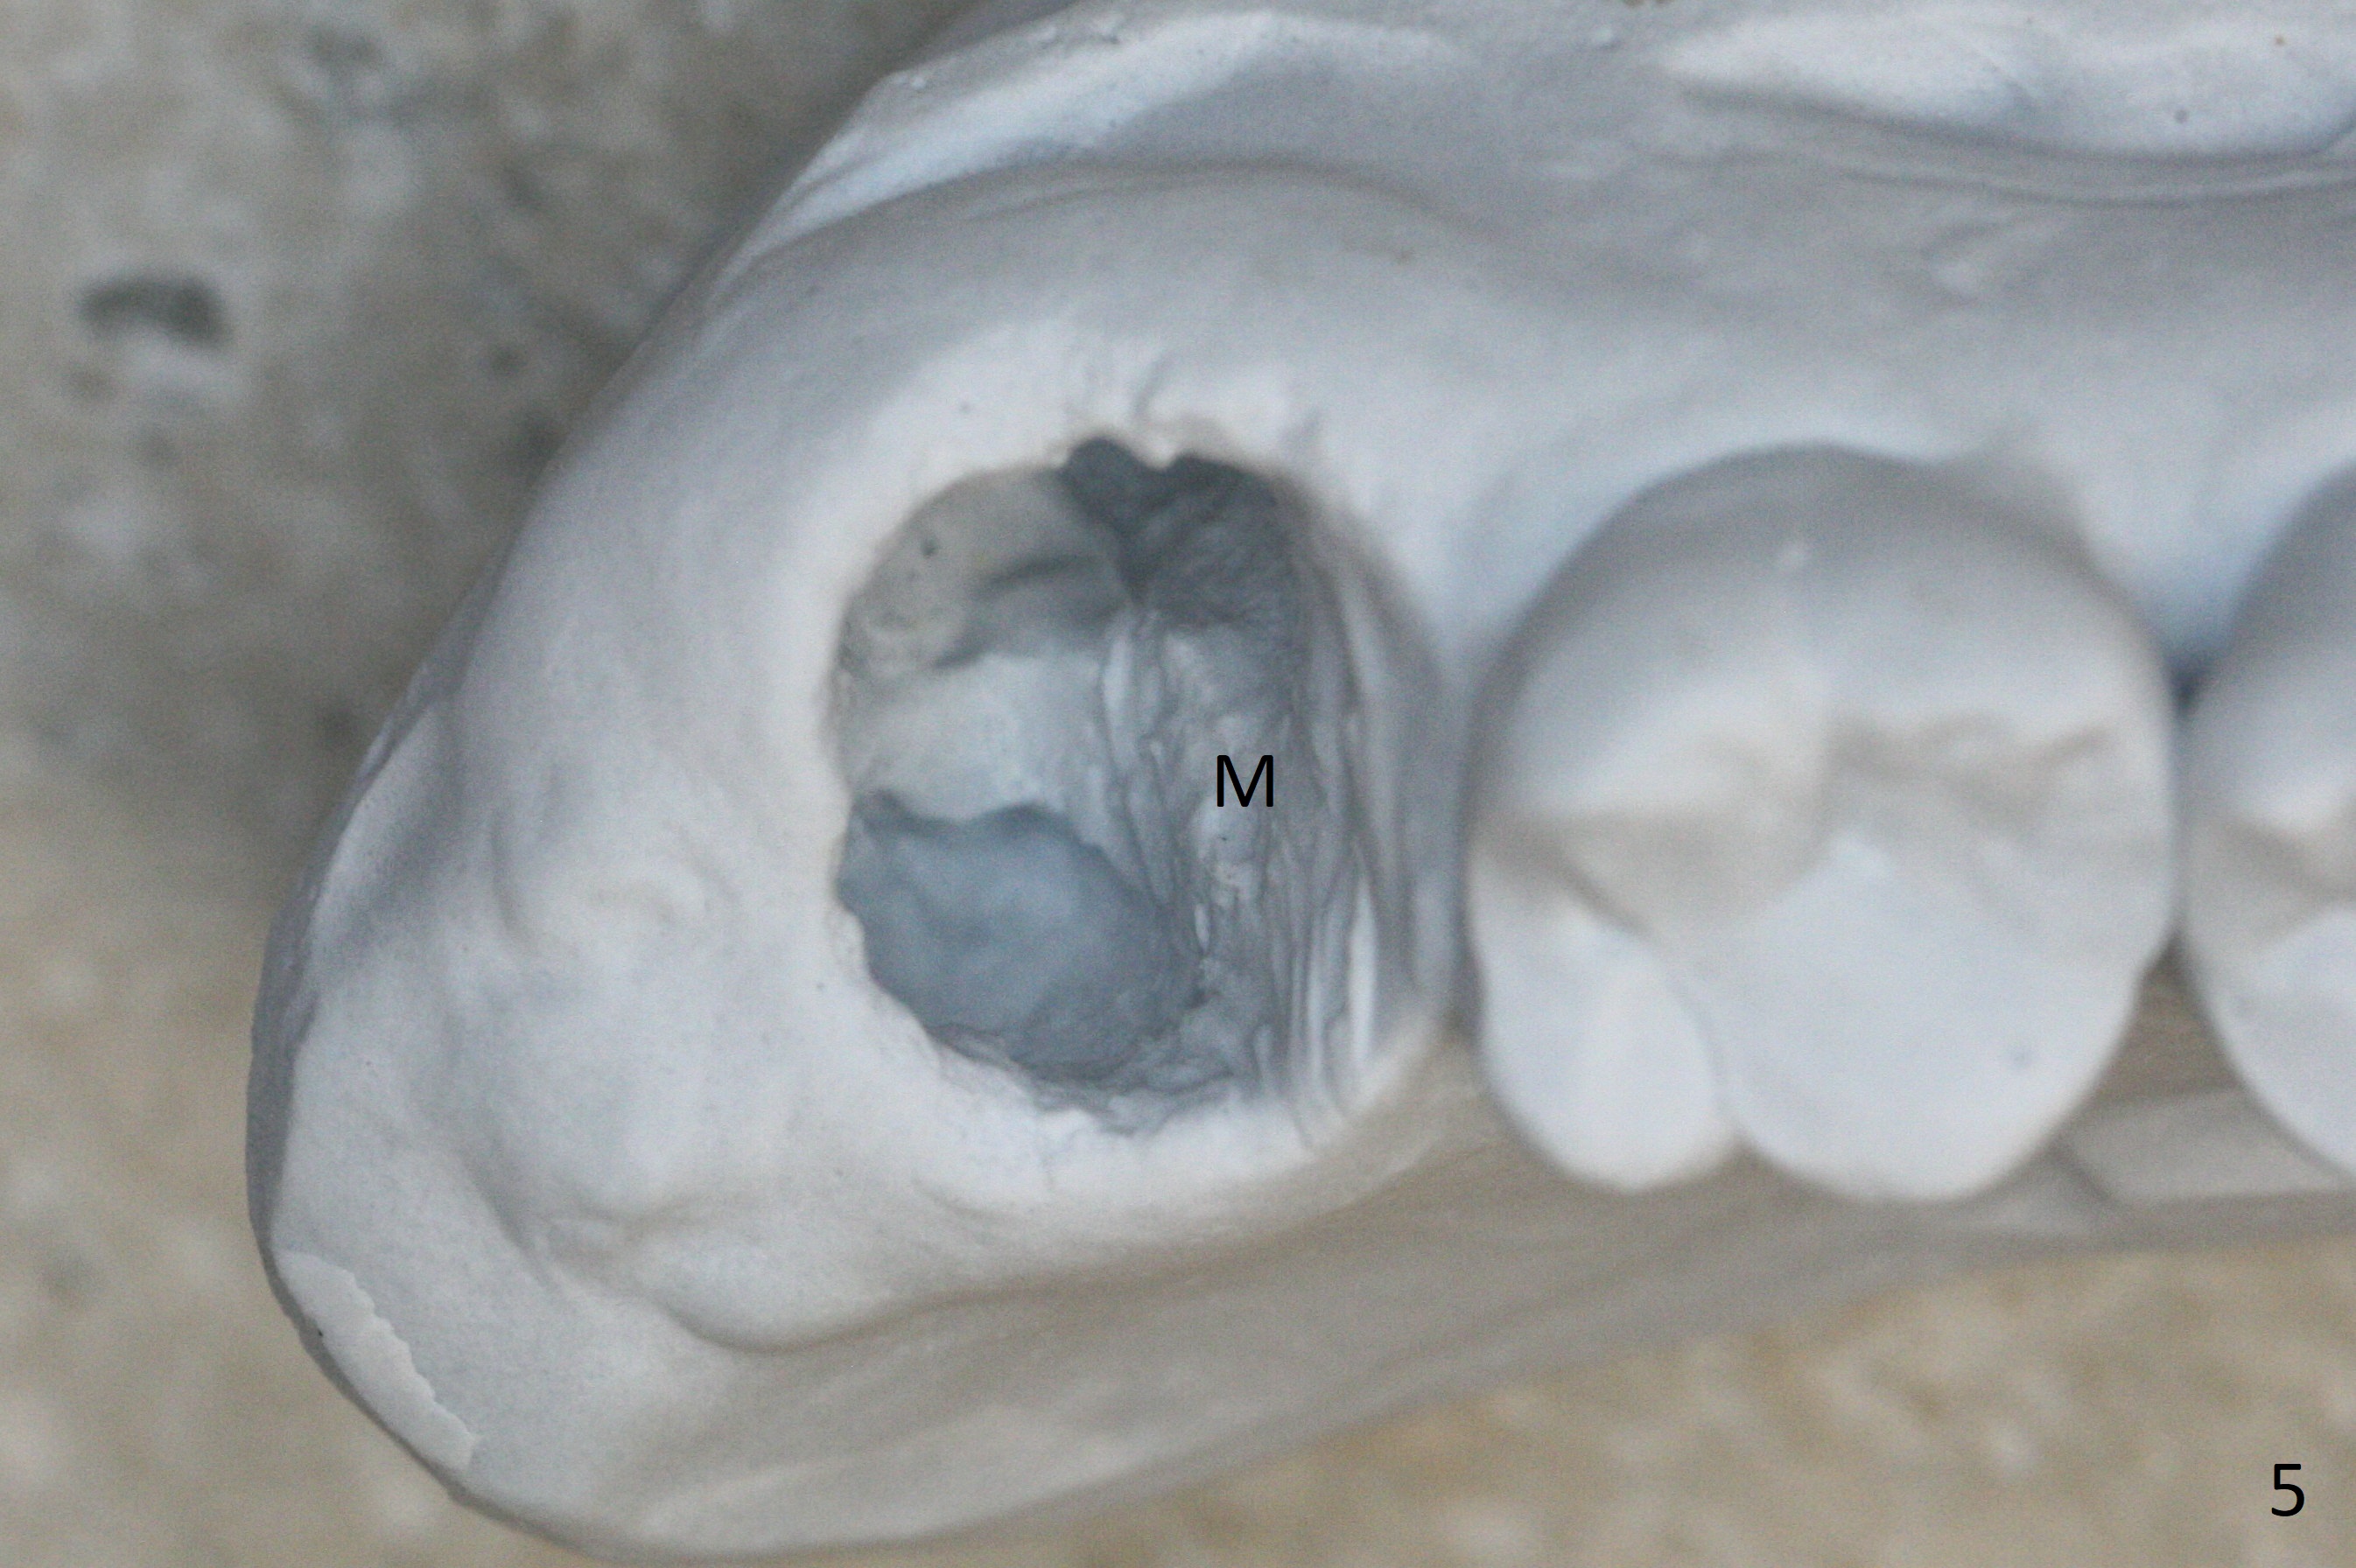

Fig.5 shows the mesial slope of the socket (M), which is more or less the center of the socket mesiodistally. If the osteotomy were set up in the red circle (Fig.6) in the mesial slope (Fig.8 green dashed line), the trajectory of 4.5x11 mm dummy implant (Fig.7) would be more ideal (Fig.8 red outline) with more native bone contact. Finally a longer IBS implant is placed (4.5x15 mm, Fig.9,10) to achieve primary stability (50 Ncm). When the provisional is removed for impression 3 months 10 days postop, the implant is found to have been placed distopalatally (Fig.13), which should have been avoided. It appears essential to use guide for a distal implant. It is agonizing to re-encounter the off-axial implant (Fig.14) and the distopalatal access hole (Fig.15) 1 year post cementation. It is also amazing that the abutment screw has not loosened. A fair-sized piece of bone graft has just been removed buccally (Fig.15,16). The patient complains of sensitivity 2 years 3 months post cementation, although there is no abnormality around the implant crown. Guided surgery is essential to avoid restoration complication. There is no thread exposure nearly 3 years post cementation; in fact the apical portion of the abutment is covered by the bone (Fig.17,18).